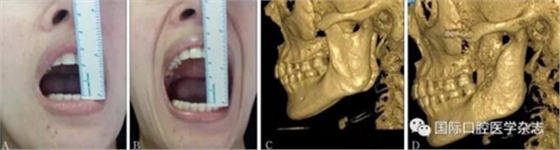

A:術(shù)前開(kāi)口度;B:術(shù)后開(kāi)口度;C:術(shù)前影像學(xué)檢查片;D:術(shù)后影像學(xué)檢查片。

圖 20 顴弓骨折修復(fù)術(shù)前后對(duì)比